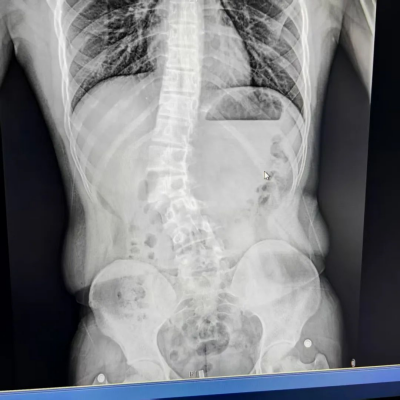

两年前,小林的母亲发现孩子双肩不等高、背部肌肉不对称,原以为是姿势不良所致,经医院详细检查,确诊为青少年特发性脊柱侧弯(AIS)。影像显示,其脊柱以腰2为中心向右侧突出,范围从胸11延伸至腰4。

患者为青少年特发性脊柱侧弯,以腰2为中心向右侧突出,从胸11延伸至腰4